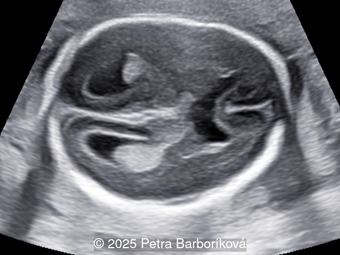

A 35-year-old secundigravida was referred to our unit at 20 weeks gestation for evaluation of suspected fetal skeletal abnormalities. Her first child was healthy, and her personal and family history were otherwise unremarkable. Two years later in a subsequent pregnancy, the patient presented for ultrasound evaluation. This examination was performed at 13 weeks of gestation and demonstrated the following findings: